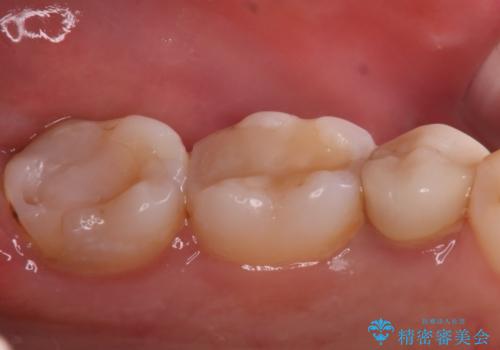

奥歯に虫歯があると言われた セラミッククラウンでキレイで長持ちする歯へ

担当医 榊原康平